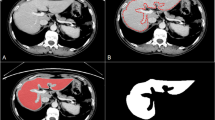

To evaluate diagnostic performance of a radiomics model for classifying hepatic cyst, hemangioma, and metastasis in patients with colorectal cancer (CRC) from portal-phase abdominopelvic CT images.

This retrospective study included 502 CRC patients who underwent contrast-enhanced CT and contrast-enhanced liver MRI between January 2005 and December 2010. Portal-phase CT images of training (n = 386) and validation (n = 116) cohorts were used to develop a radiomics model for differentiating three classes of liver lesions. Among multiple handcrafted features, the feature selection was performed using ReliefF method, and random forest classifiers were used to train the selected features. Diagnostic performance of the developed model was compared with that of four radiologists. A subgroup analysis was conducted based on lesion size.